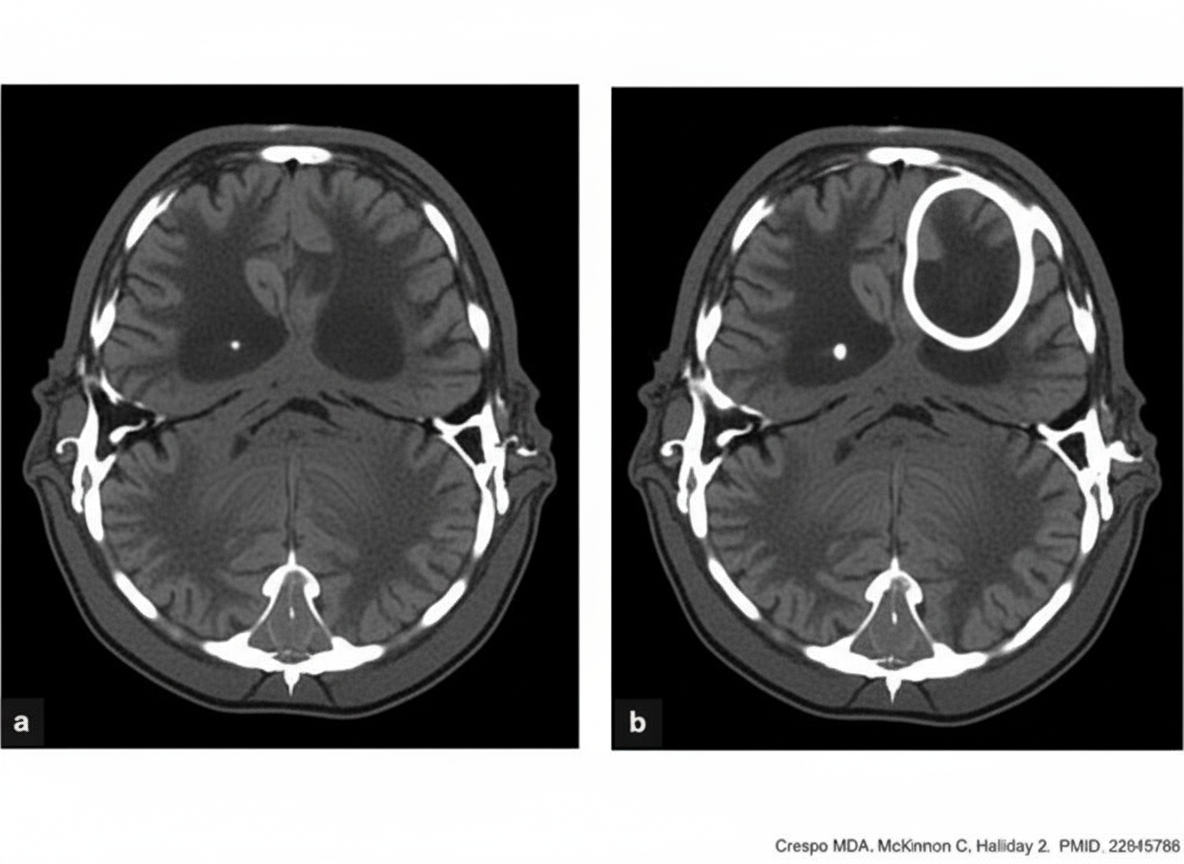

A patient presents with foul-smelling ear discharge and convulsions. What is the appropriate management for this patient, given the CECT findings?

Explanation: ***Abscess drainage followed by Modified Radical Mastoidectomy (MRM)*** - **Brain abscess** with raised **intracranial pressure** requires immediate drainage to prevent **herniation** and neurological deterioration. - After stabilizing the patient with abscess drainage, **MRM** is performed to remove the **mastoid source** and prevent recurrence. *Modified Radical Mastoidectomy (MRM) followed by abscess drainage* - Performing **MRM first** delays treatment of the life-threatening **intracranial complication** and may worsen **raised ICP**. - The **brain abscess** poses immediate risk of **herniation** and requires priority management over the mastoid source. *Myringoplasty* - This procedure only repairs the **tympanic membrane** and does not address the underlying **chronic suppurative otitis media (CSOM)**. - Completely inadequate for managing **intracranial complications** like brain abscess requiring urgent neurosurgical intervention. *Modified Radical Mastoidectomy (MRM) only* - While **MRM** addresses the **mastoid source**, it ignores the life-threatening **brain abscess** causing convulsions. - **Intracranial complications** require **neurosurgical drainage** first to prevent immediate mortality from raised ICP.